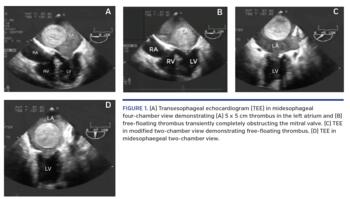

A 75-year-old female with a history of rheumatic heart disease was admitted due to a syncopal episode. During the past 2 months, she reported 2 other sudden, brief episodes of syncope consistent with drop attacks. There were no premonitory symptoms suggestive of vasovagal syncope. Physical examination demonstrated an irregular rhythm and an apical diastolic murmur. Telemetry demonstrated her rhythm to be atrial fibrillation with a controlled rate. Electroencephalogram did not demonstrate seizure activity. Transesophageal echocardiography demonstrated severe mitral stenosis with a 5 x 5 cm, free-floating, left atrial thrombus intermittently obstructing the mitral valve orifice, which was bouncing off the mitral valve much like a pinball. These findings were confirmed on transesophageal echocardiography (Figures 1-4 and Video 1). The patient underwent removal of the thrombus along with mitral valve replacement, and was placed on chronic anticoagulation. She did not have any further syncopal episodes at 1-year follow-up exam.